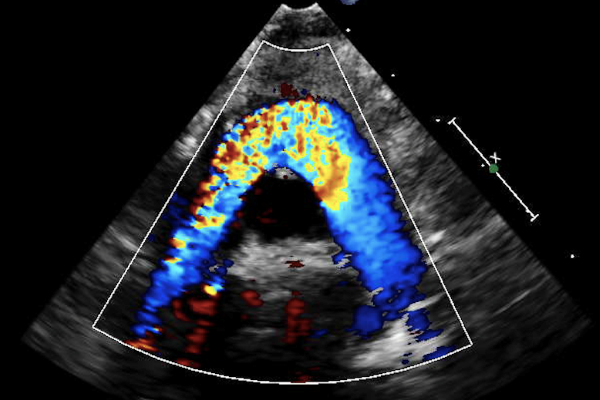

The Echocardiography Laboratory in the Labatt Family Heart Centre provides diagnostic cardiac ultrasound for children with suspected or known heart disease. We evaluate patients ranging from the fetus to childhood to adolescence. Using state-of-the-art equipment, ultrasounds are performed by highly skilled pediatric sonographers and interpreted by a world-class team of diagnostic physicians. We perform pediatric transthoracic echocardiograms (TTE), transesophageal echocardiograms (TEE), exercise stress echocardiograms, contrast echocardiograms, and fetal echocardiograms.